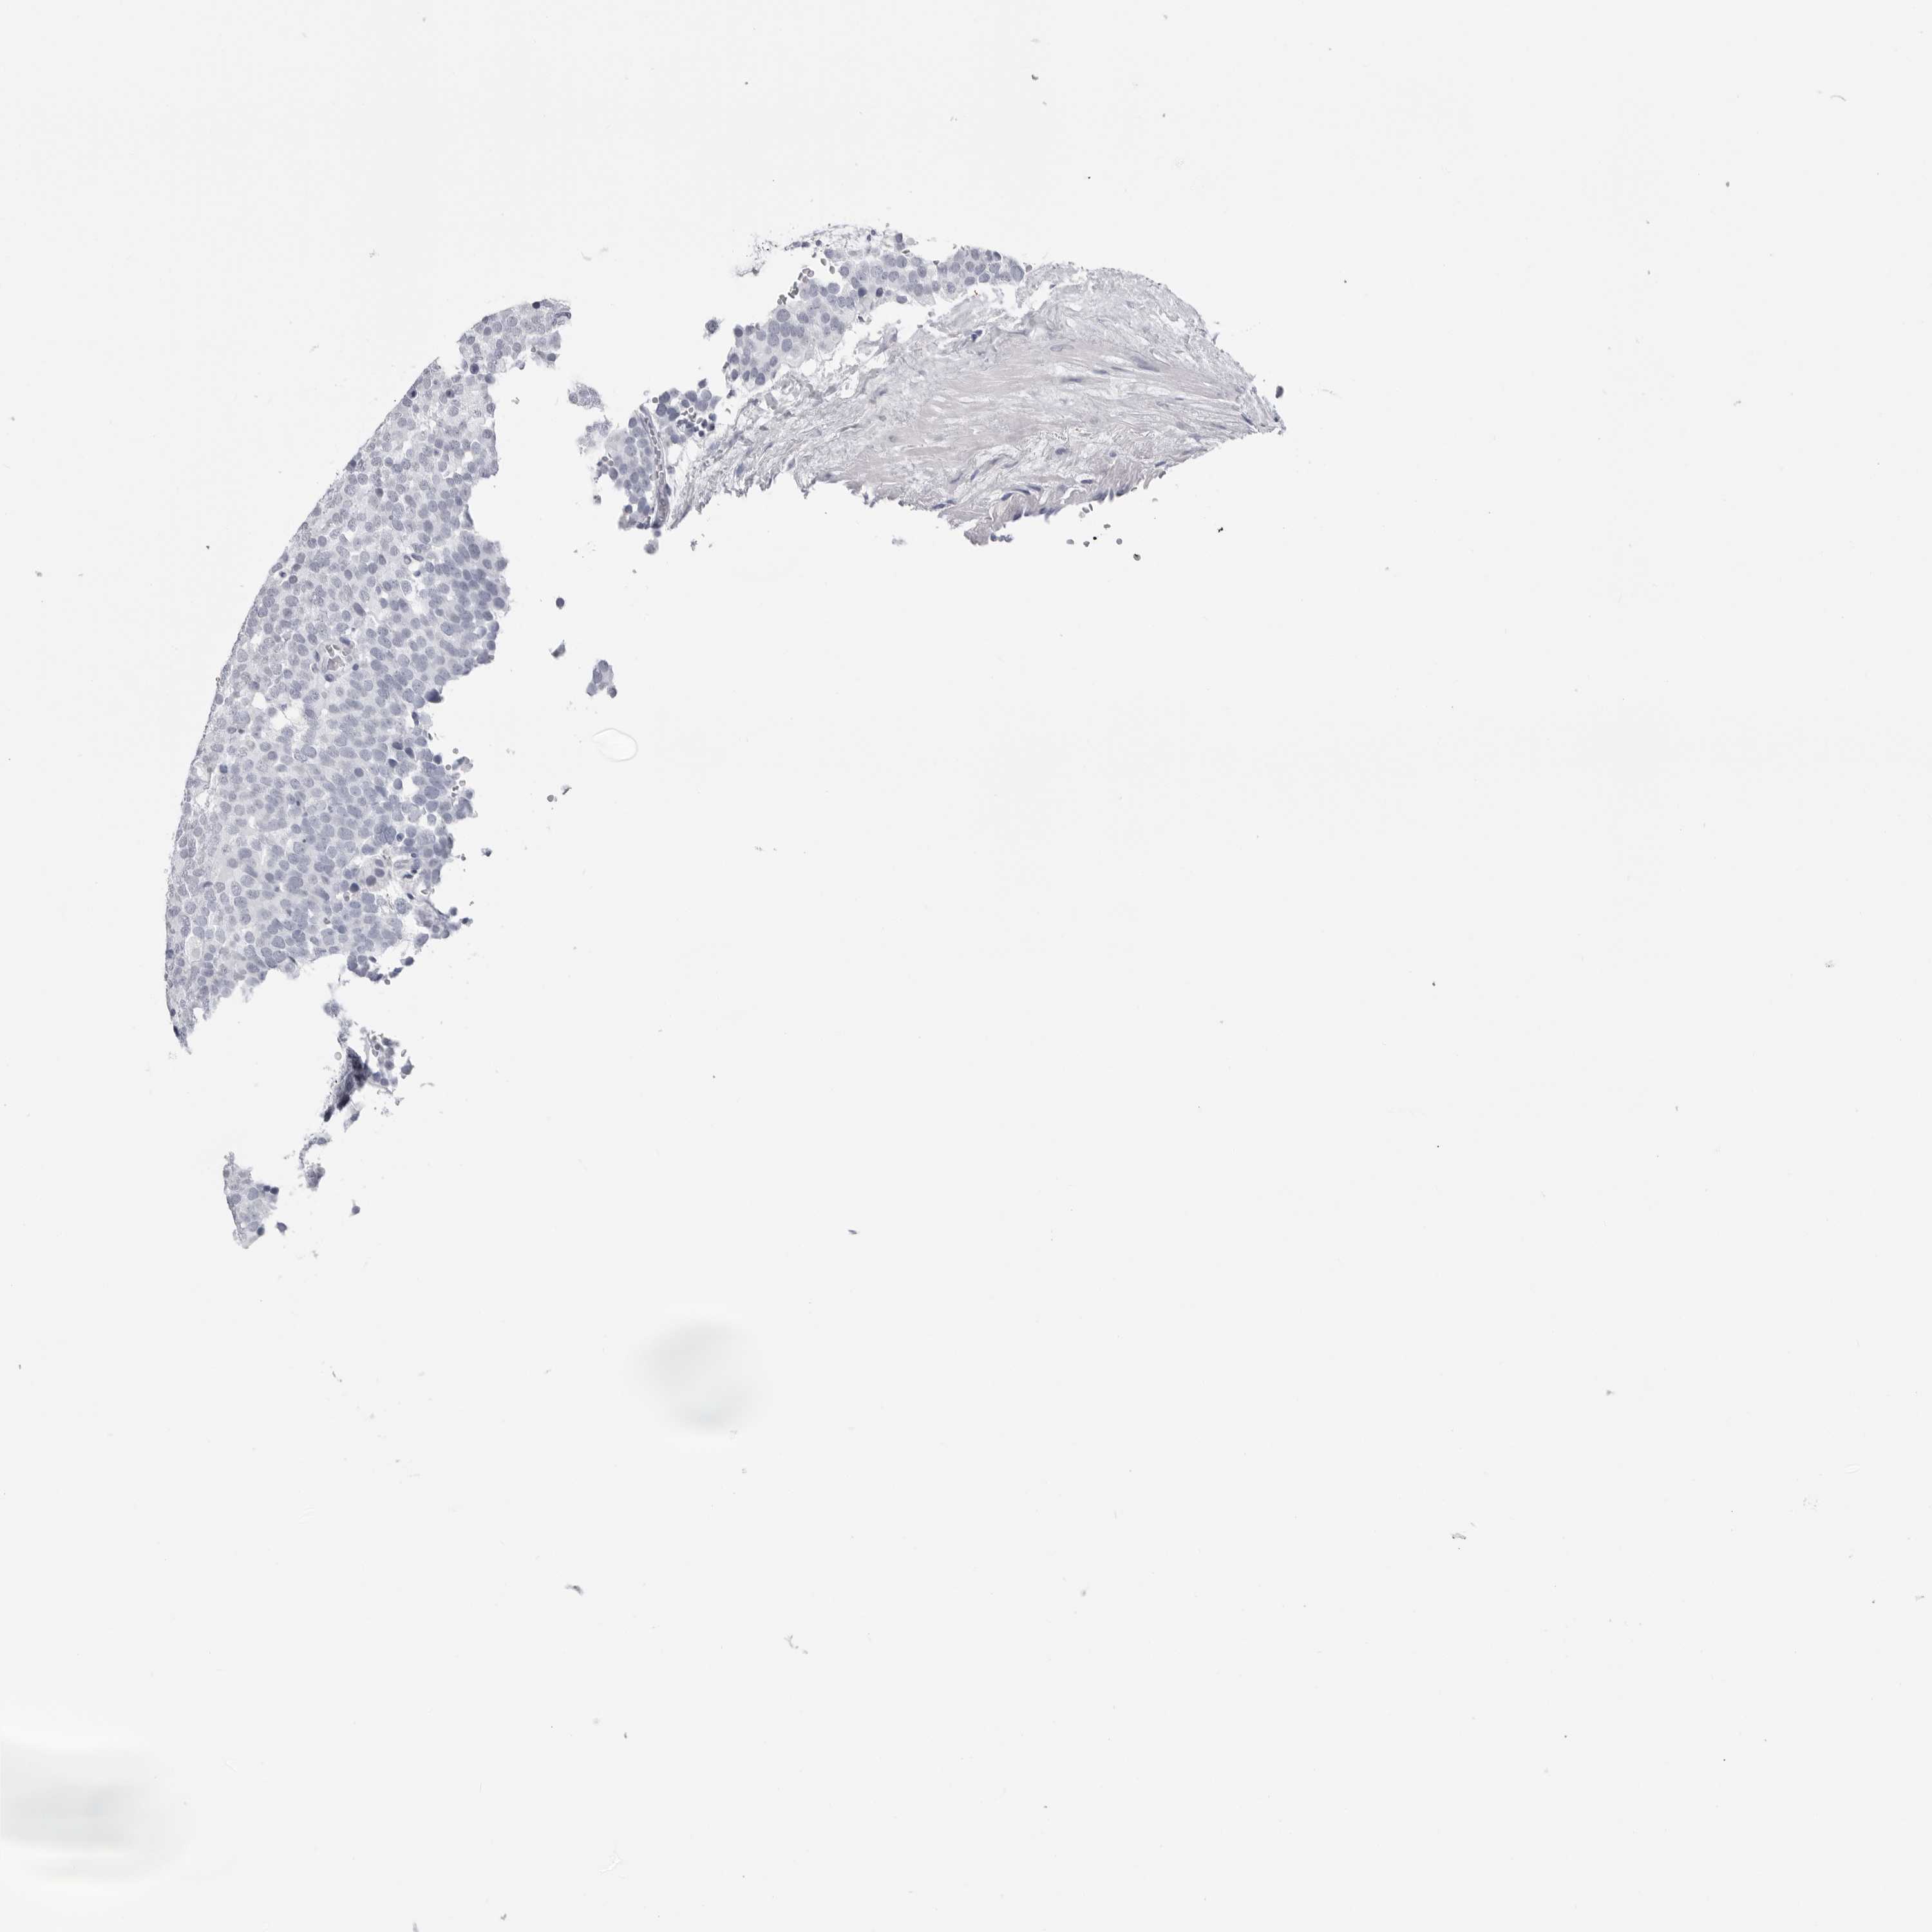

TESTIS CANCER - Protein expressioni

A mouse-over function shows sample information and annotation data. Click on an image to view it in a full screen mode. Samples can be filtered based on level of antibody staining by selecting one or several of the following categories: high, medium, low and not detected. The assay and annotation is described here.

Note that samples used for immunohistochemistry by the Human Protein Atlas do not correspond to samples in the TCGA dataset.

Antibody stainingi

Antibody staining in the annotated cell types in the current human tissue is reported as not detected, low, medium, or high, based on conventional immunohistochemistry profiling in selected tissues. This score is based on the combination of the staining intensity and fraction of stained cells.

Each image is clickable and will lead to virtual microscopy that enables deeper exploration of all samples and also displays staining intensity scores, fraction scores and subcellular localization as well as patient and tissue information for each sample.

Antibody HPA046875

Antibody CAB026358

Seminoma, NOS

Carcinoma, Embryonal, NOS